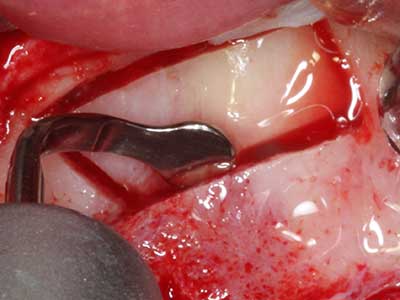

When surgical procedures are performed on bone in the immediate vicinity of sensitive structures such as blood vessels or nerves, rotary instruments pose a significant risk of iatrogenic injury. Piezoelectric devices can be helpful for preparation of bone covers and removal of hard tissue close to nerves, particularly for exposure of nerves after iatrogenic injury but also during nerve lateralization for resective and reconstructive procedures or implant placement (Fig. 17-20). Light contact between the piezotip and the nerve does not generally result in damage but proceeding incautiously with saw-like motions or attachments where a residual bone substrate remains may cause temporary or even permanent nerve damage. However, the risk of damage is considered to be substantially lower than when using saws or milling instruments (Pereira, Gealh et al. 2014).

Fig. 18: Preparation of a cortical cover with the piezo bone saw (Piezomed, W&H).

Fig. 19: Surgical site after neurolysis and removal of osteoma.